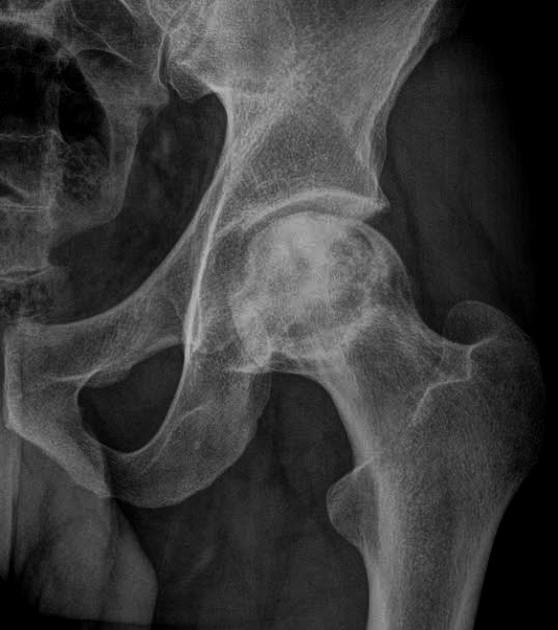

Associated with ischemic necrosis of bone. Ischemia results from poor blood supply to the bone. Affects the epiphyses and may be mistaken for tuberculosis of the skeletal system. Tends to occur in males between the ages of 5 to 10 years and often follows injury to the affected hip. Radiographically the bone in the center of the epiphysis is fragmented and the head of the femur is flattened.

Legg-Perthes Disease